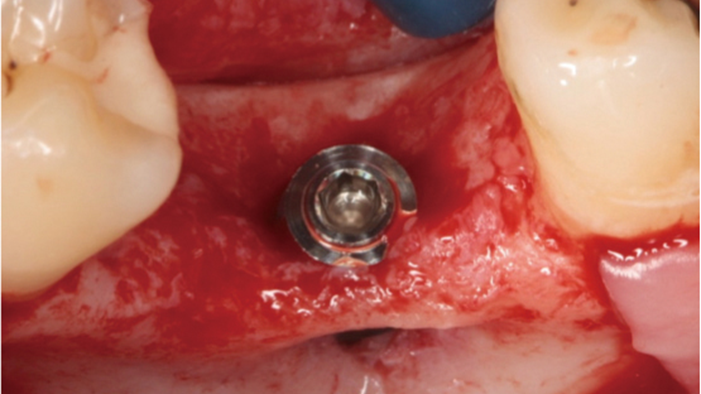

Clinical case: # 46 implant placement & GBR using i-Gen membrane for significant vertical resorption & mixed bone defect

- Courtesy of Dr. Iulian Filipov, Romania -

AnyRidge, mandibular posterior, i-Gen, resorption, bone defect, bone regeneration, space management, #46, GBR, Dr. Iulian Filipov

“AnyRidge KnifeThread achieves excellent stability in regenerated bone & even in only 3mm bone height!”